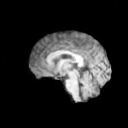

The results presented in Table 1 and 2 show our proposed method’s performance on unconditional 3D brain MR and chest CT image generation. Our proposed approach not only outperforms most comparing methods in FID and MS-SSIM metrics, it also has the lowest inference GPU memory footprint at a resolution of and was the only diffusion-based method that could be trained at a resolution of . Operating in the wavelet domain and profiting from the reduced spatial dimension also results in a relatively short inference time of / at the respective resolutions. Compared to the results presented in [23], we did not find that incorporating wavelet information into the network’s feature space (WavU-Net) increased the model’s performance. Qualitative results of our proposed method (WDM) are shown in Fig. 2 and 3. A qualitative comparison of samples produced by all evaluated methods can be found in the Supplementary Material.